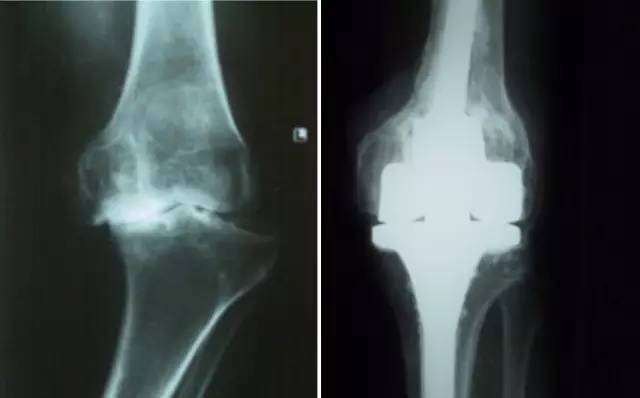

铰链式人工膝关节置换手术(HK)膝关节周围韧带严重破坏

国内首例膝关节置换术后Felix IIB型胫骨假体周围骨折翻修术